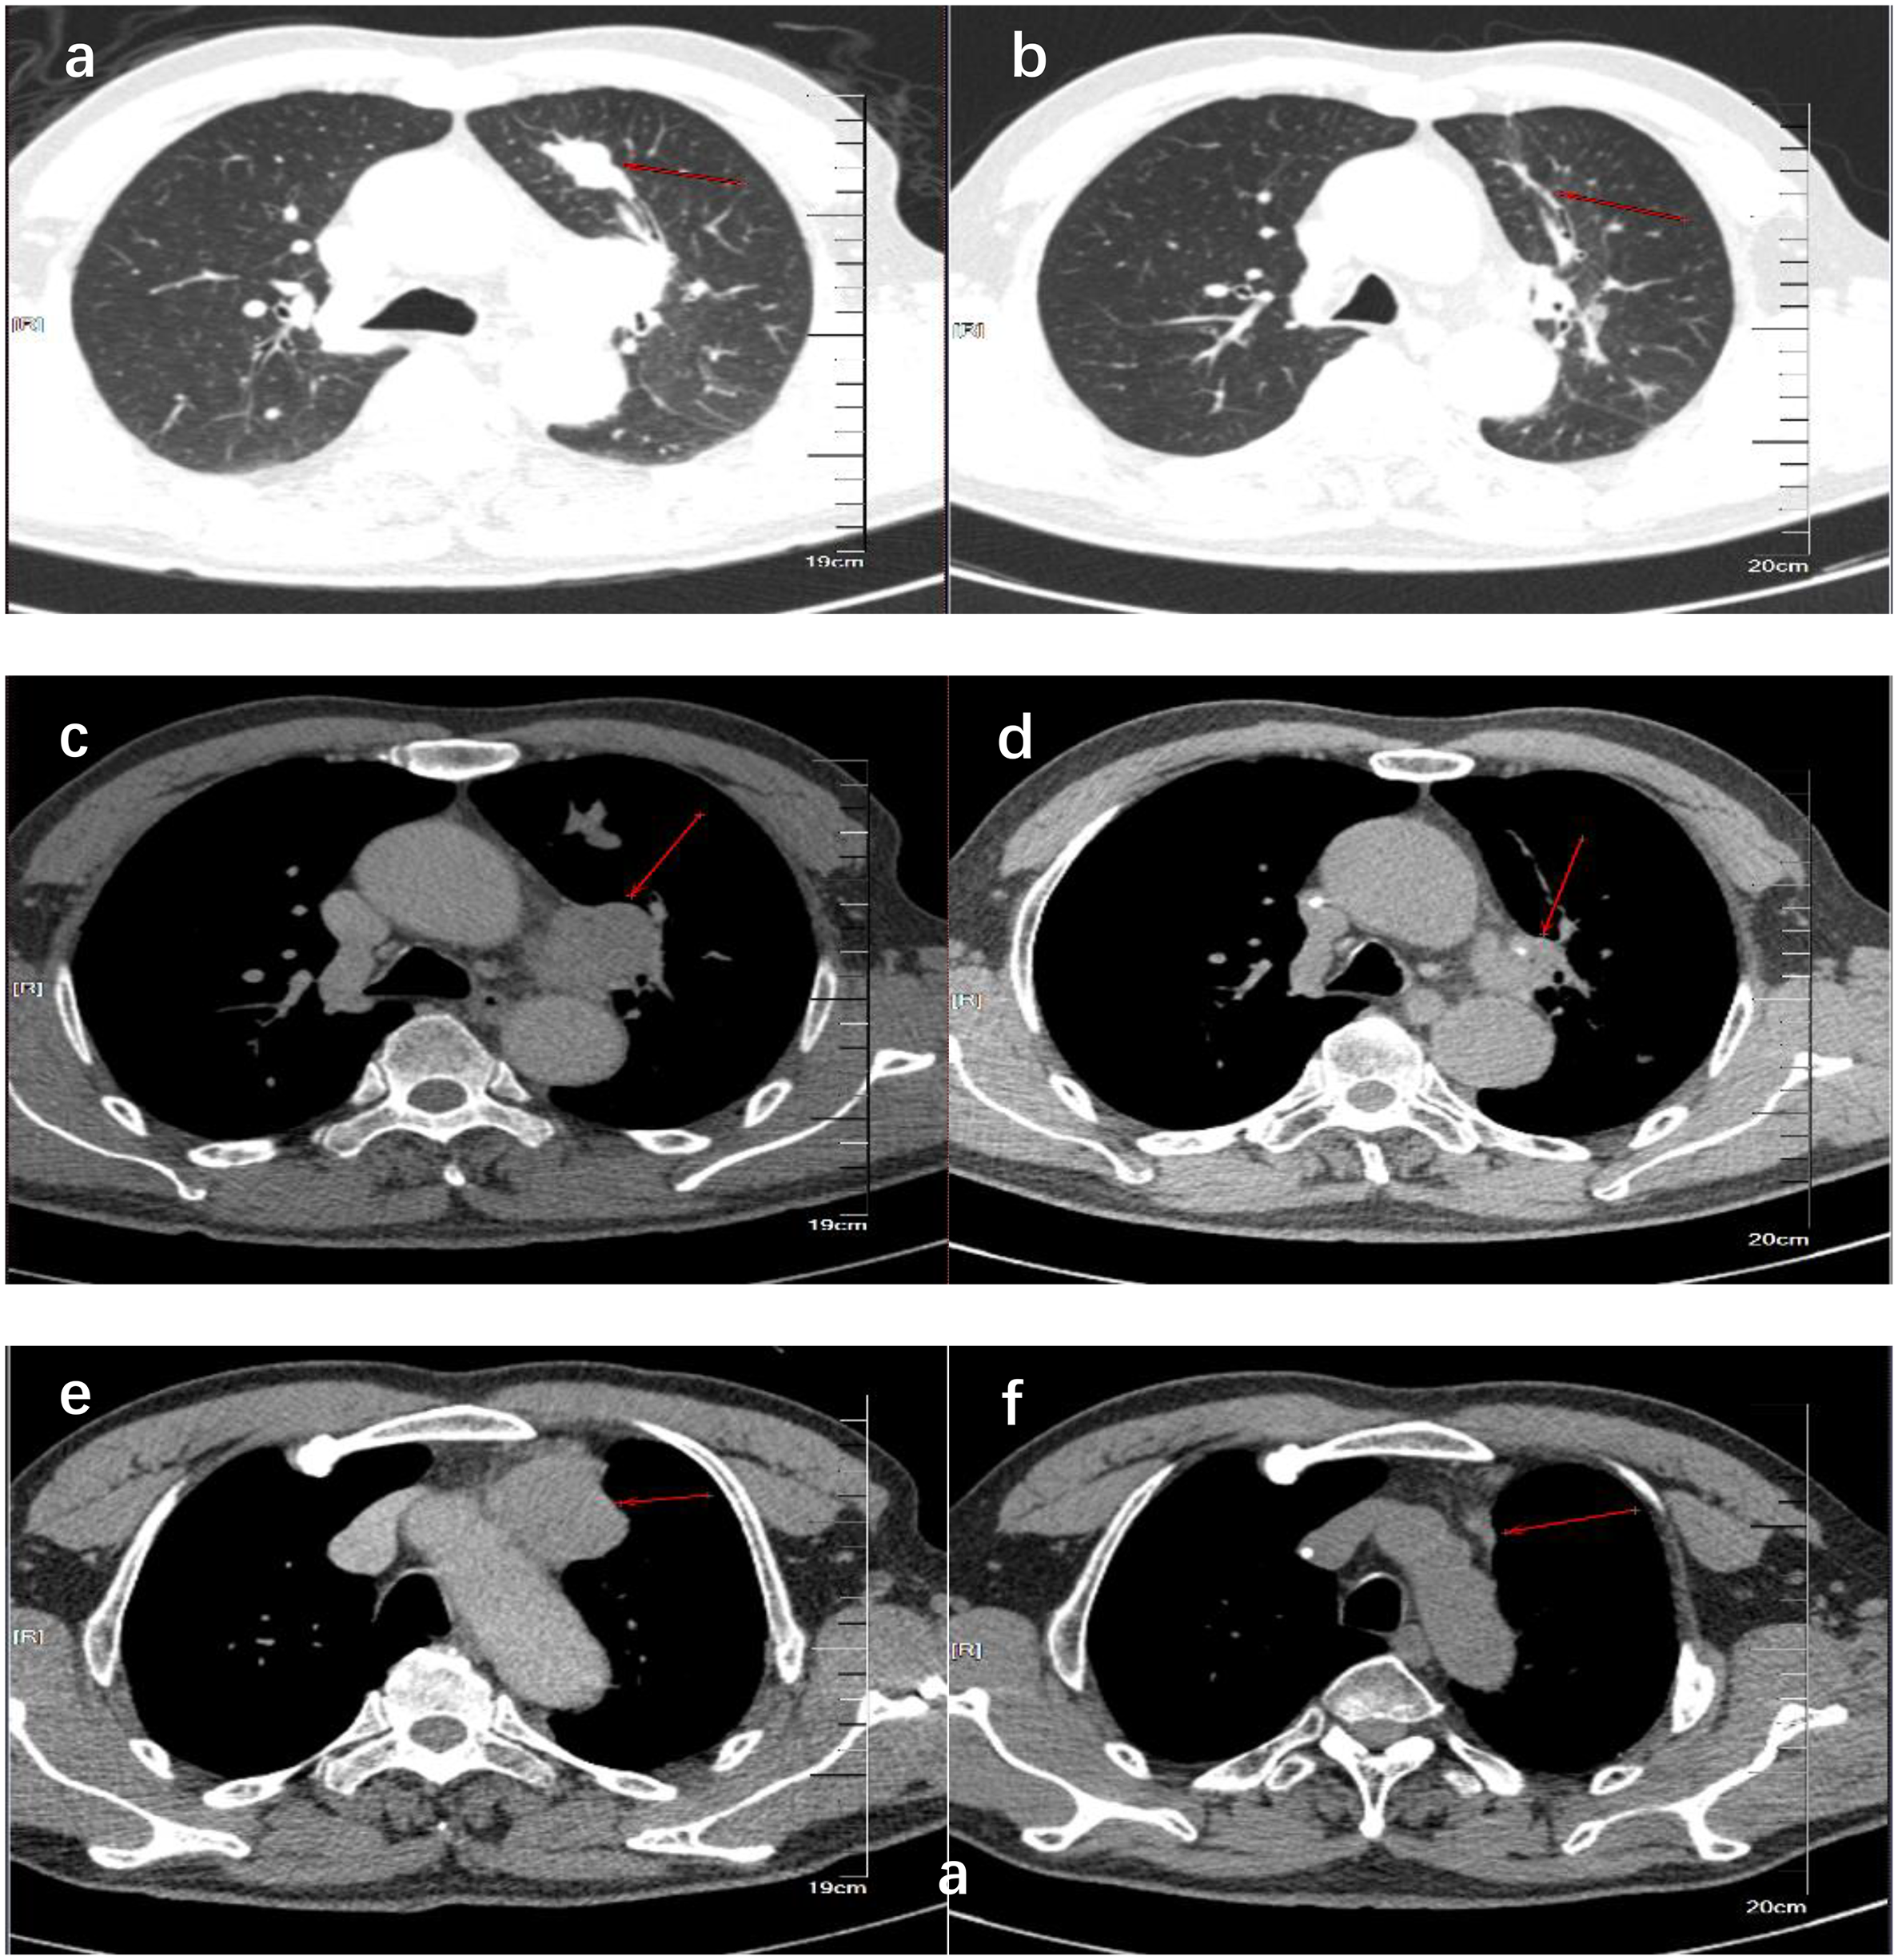

We present the case of a 69-year-old man with a history of 20 pack-years of smoking, who underwent CT scan due to 4 months of a dry cough under no obvious inducement on 14 December 2018. The CT revealed a dense mass in the upper lobe of the left lung which measured approximately 2.8 cm × 1.5 cm in size; moreover, there were soft-tissue density lesions in the anterior mediastinum and left hilar area, which sized about 4.3 cm × 3.1cm and 3.4 cm × 3.0 cm, respectively (Figures 1A, C, E). The result of bronchoscopic transbronchial lung biopsy supported SCLC based on the immunohistochemistry analysis that revealed a positive staining for pan-cytokeratin (CKpan), thyroid transcription factor 1 (TTF-1), protein phosphatase 1 (Ki-67) (approximately 90%), synaptophysin (Syn), and cluster of differentiation 56 (CD56) and a negative staining for Tumor prot ein 63 (P63), Cytokeratins (CKs) 5 and 6 (CK5/6), and cytokeratin (CK7). Therefore, he was diagnosed with limited-stage SCLC and treated with concurrent cisplatin and etoposide chemotherapy combined with thoracic radiotherapy and standard prophylactic brain radiation. The last time for treatment was 17 July 2019, and the CT scan reported that the lesions size was about 1.1 cm × 0.5 cm in the upper lobe of the left lung and 2.0 cm × 1.3 cm and 1.9 cm × 1.8 cm in the anterior mediastinum and left hilar area, respectively (Figures 1B, D, F). Subsequently, the patient had regular follow-up examinations.

Figure 1

CT showed the comparison of lung lesions before (A, C, E) and after (B, D, F) the treatment of concurrent chemoradiotherapy. (A, B) show the tumor location of the primary lesion in the left upper lobe before and after treatment. (C, D) show the location of the tumor before and after treatment of the left hilar lymph node metastases. (E, F) show the tumor location before and after treatment of anterior mediastinal lymph node metastases.